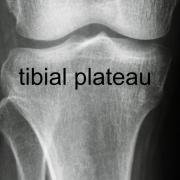

The tibia and femur bones form the main articulation of the knee joint, and the tibia also articulates with the fibula bone at the outer side of the knee.

Between the tibia and femur is the meniscus, which accommodates the rounded ends of the femur and the flattened top of the tibia. The two cruciate ligaments reach between the two bones right in the centre of the knee.